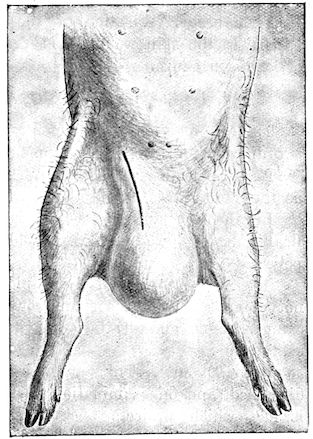

Fig. 1.—Rachitis in a young goat.

Fig. 1.—Rachitis in a young goat.